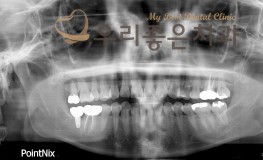

임플란트